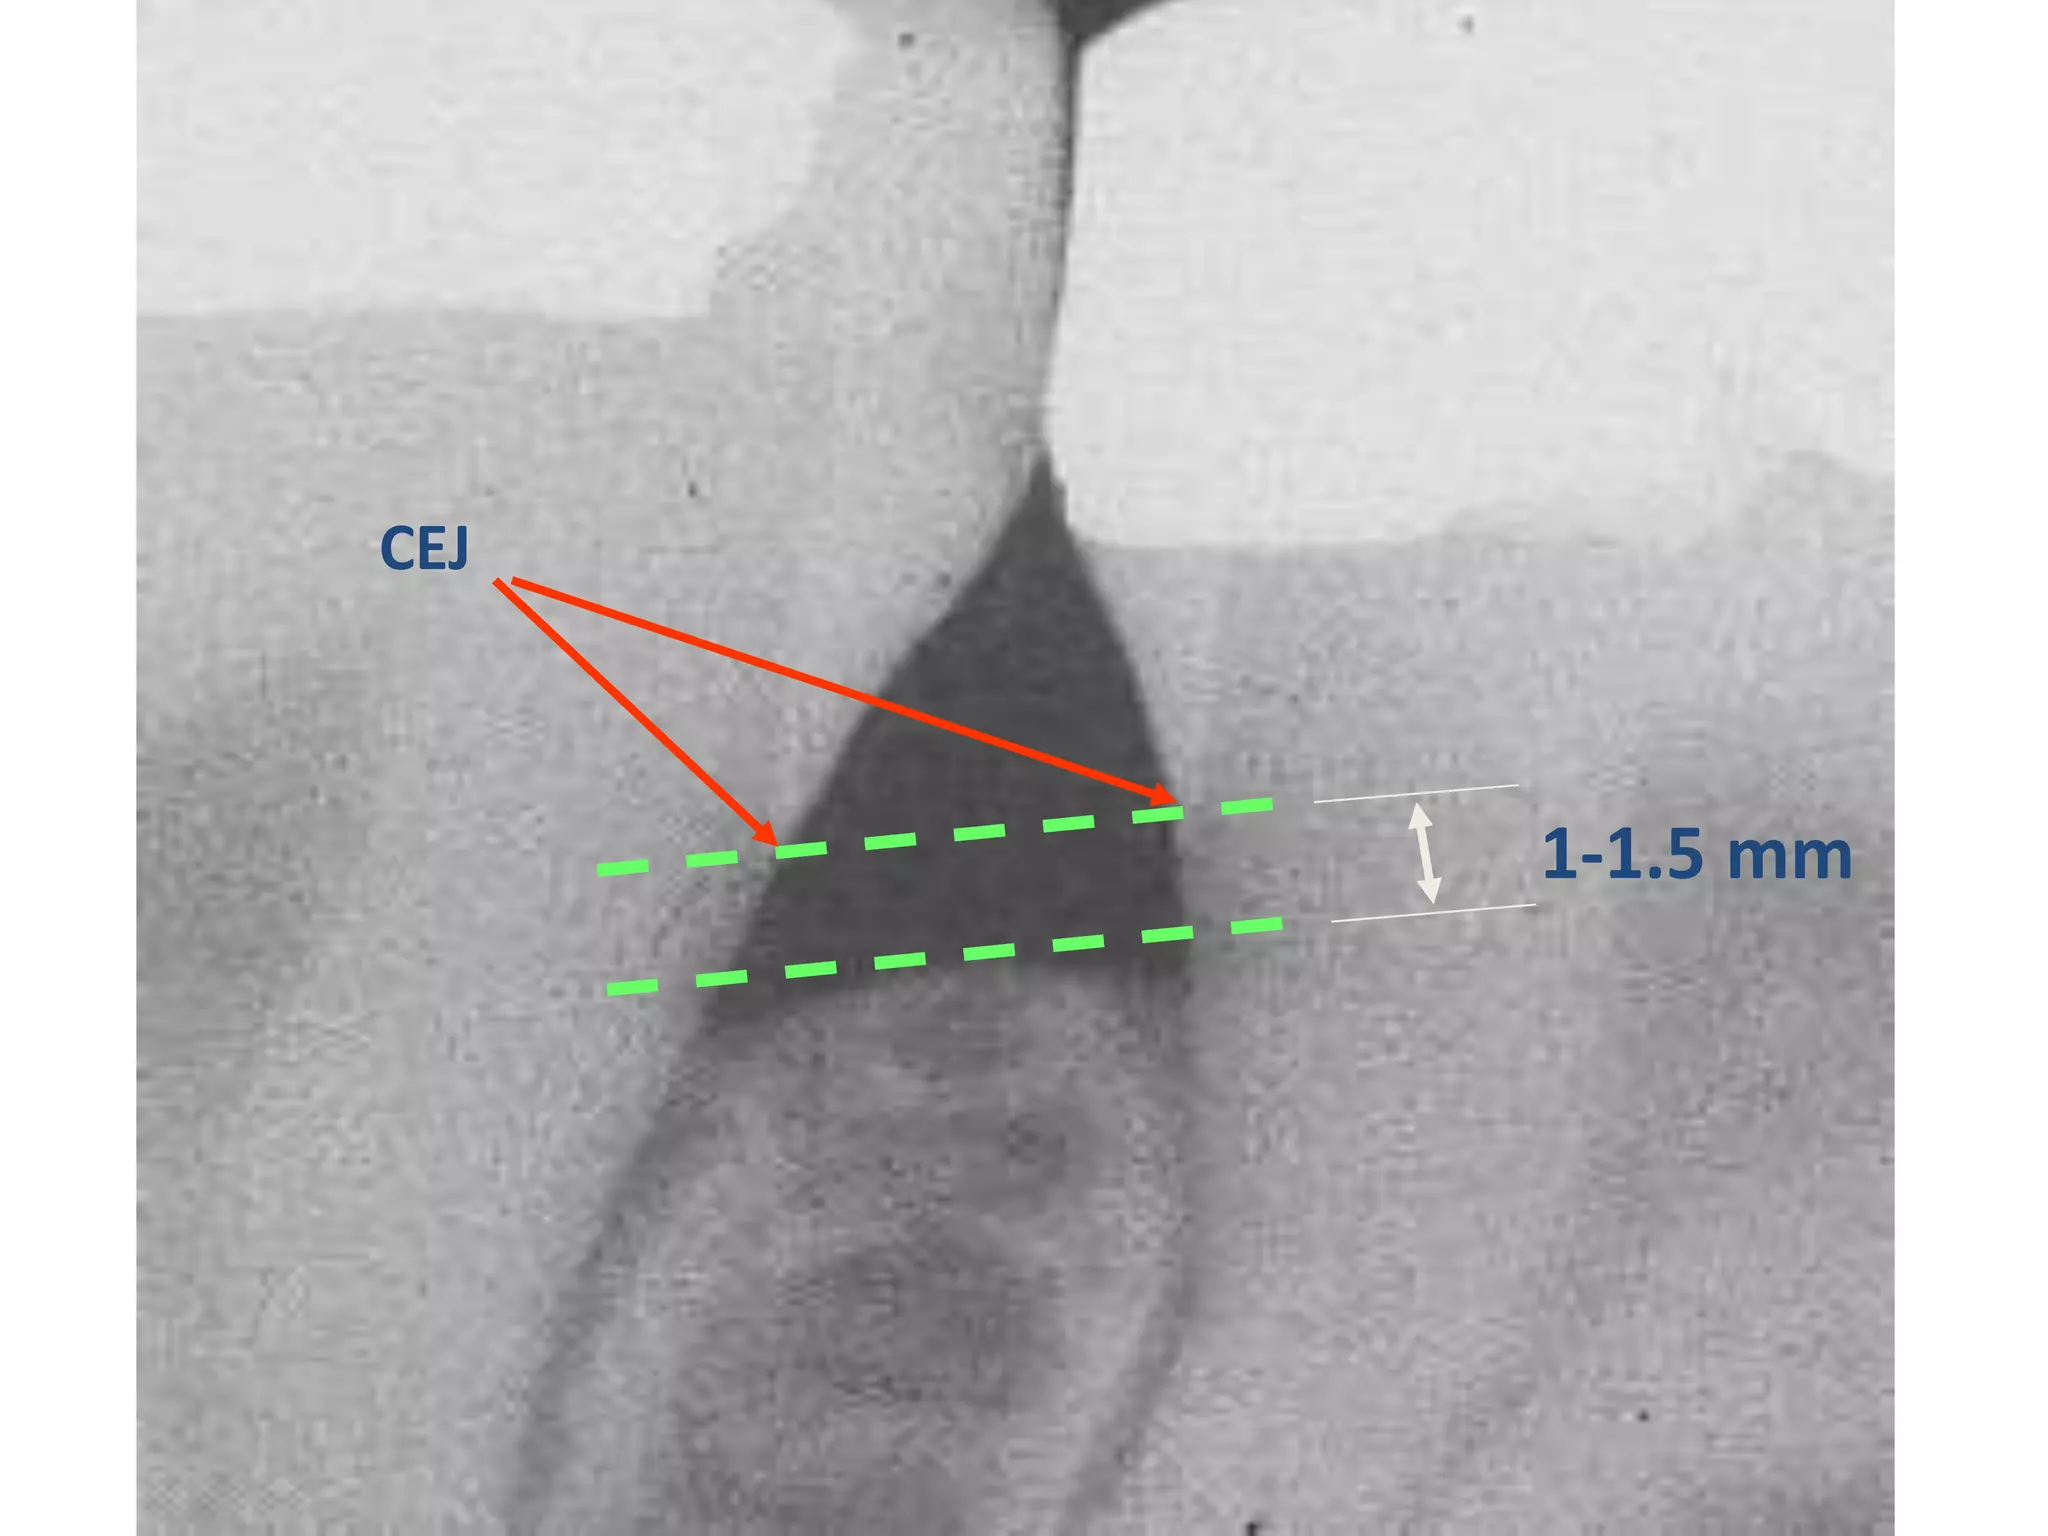

Periodontitis

Normal Anatomy:

Alveolar crest corticated

1-1.5 mm from crest to CEJ

Parallel to line between CEJ’s

Crest is pointed anteriorly

Corticated alveolar crests

CEJ

1-1.5 mm

Alveolar crests more

pointed anteriorly